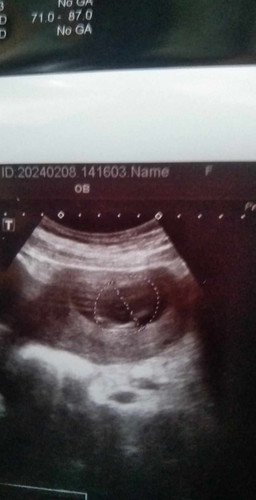

อยากทราบเรื่องเรานับได้16,วิคเเต่หมอบอกเมื่อวาน14+2วิคเราต้องนับสัปดาห์ใหม่ใหมคะ

พอดีอยากทราบค่ะว่าตอนนี้เราได้16วิคเเต่เมื่อวานหมอไปอัลตร้าซาวด์หมอบอกว่า14วิค เราต้องนับสัปดาห์ใหม่ใหมคะหรือว่าเอาตามที่หมอบอก พอดีท้องเเรกอ่ะค่ะ ขอบคุณสำหรับคำตอบค่ะเเม่ๆ #